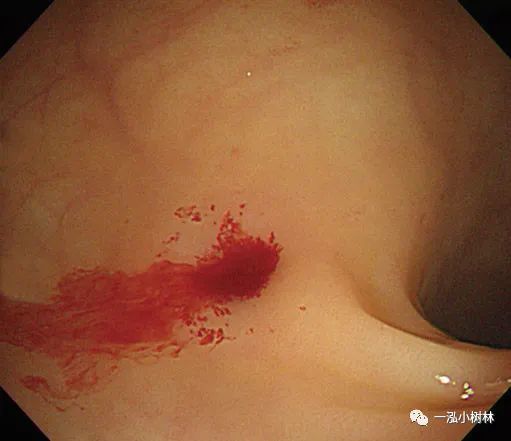

图1b 冷钳息肉摘除术后黏膜出血